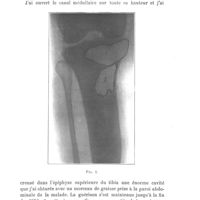

0209 - Page 203 - Séance du 29 janvier 1913. Présentations de malades. Greffe adipeuse. Résultat éloigné d'un vaste évidement du tibia traité avec succès par la greffe adipeuse en 1904. Radiographie, M. Chaput0209 - Page 203 - Séance du 29 janvier 1913. Présentations de malades. Greffe adipeuse. Résultat éloigné d'un vaste évidement du tibia traité avec succès par la greffe adipeuse en 1904. Radiographie, M. Chaput